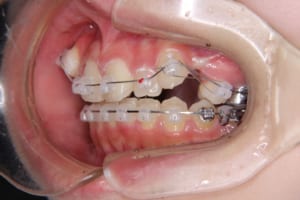

治療中

| 使用した装置 | 子どもの矯正治療(前期治療) 緩徐拡大装置 マルチブラケット装置 大人の矯正治療(後期治療/成人矯正治療) マルチブラケット装置 デーモンブラケット シルバーワイヤー 歯科矯正用アンカースクリュー(2本) ホールディングアーチ トランスパラタルアーチ |